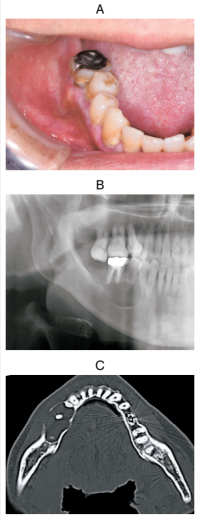

66 歳の男性。下顎右側臼歯部の腫脹を主訴として来院した。6か月前に顎骨の膨隆に気付いたが、疼痛がないためそのままにしていたという。

自発痛や下唇の感覚異常は認めない。下顎右側臼歯部に骨の膨隆を触知した。生検を行ったところ内部に軟組織の充満を認めた。初診時の口腔内写真、エックス線画像、CT及び生検時の H-E 染色病理組織像を別に示す。

適切な治療法はどれか。1つ選べ。